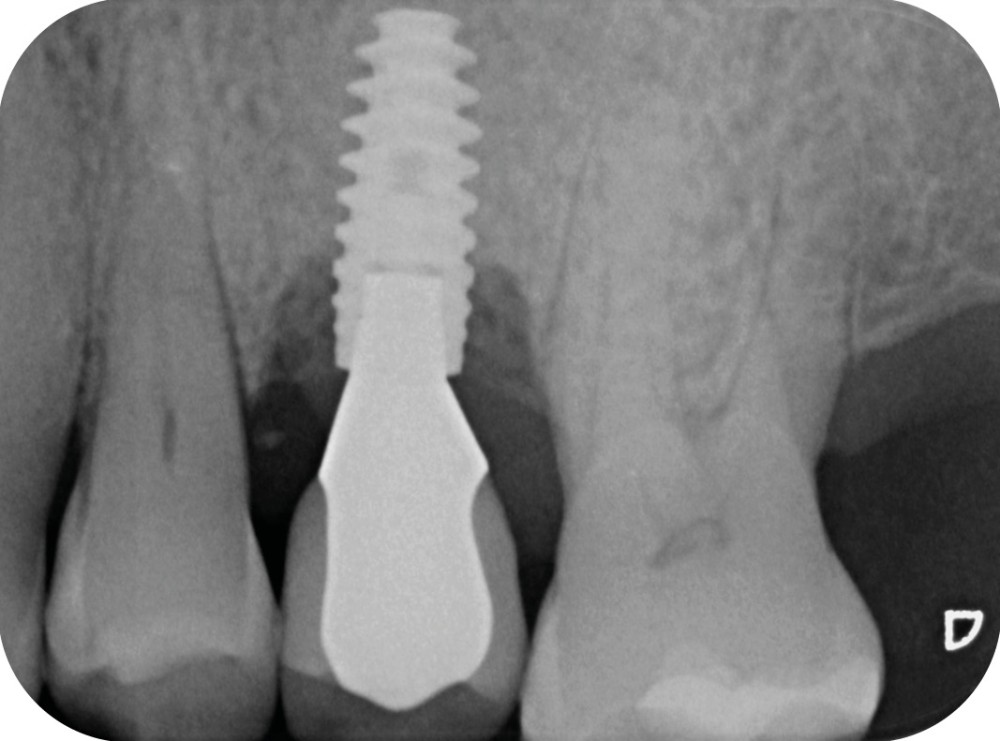

- Péri-implantite diagnostiquée en 2020

Chez cette patiente, le traitement de la péri-implantite a été réalisé à l’aide d’une technique de régénération osseuse guidée péri-implantaire, dont l’indication a été principalement motivée par la morphologie du défaut osseux. Au-delà de la maîtrise du geste chirurgical, le bon résultat obtenu à trois ans est intimement lié à sa coopération en termes de suivi et de contrôle de plaque.